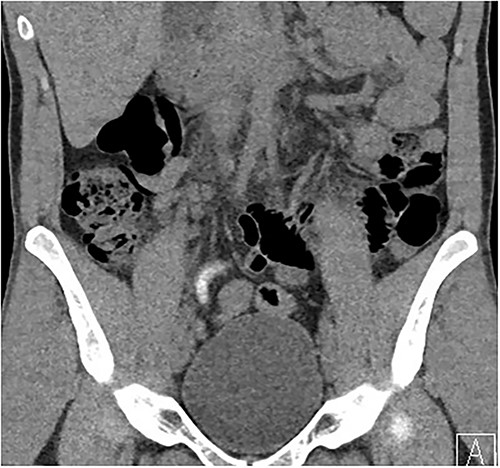

Two days following stent removal, the patient developed acute onset right lower quadrant and flank pain. A non-contrast CT of the renal tract was obtained to assess for procedure or stone-related complications. The scan demonstrated two distinct retained stones within the proximal right ureter, with associated moderate ureteronephrosis. Additionally, within the right lower quadrant of the abdomen, a radiopaque vermiform entity was demonstrated (Figs 1–3). This entity was not pathological, however, represented a normal appendix that had, consequent to contrast administration during a urological procedure, become filled with contrast secondary to vicarious contrast excretion.

Sagittal imaging, depicting the base of structure arising from the caecum.